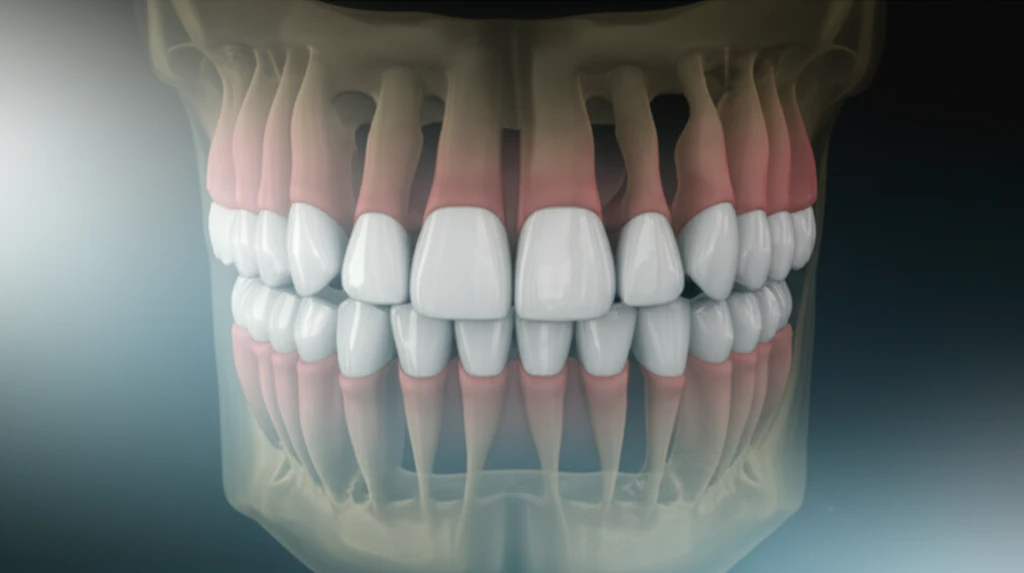

The journey to a perfect smile often involves moving teeth, and incisor retraction is a key technique. This involves carefully moving the front teeth backward to correct overbites, crowding, or other alignment issues. However, moving teeth isn't just about aesthetics; it's about understanding the biological responses within your mouth. The teeth are embedded in bone, and the process of retraction can affect the length of your teeth and the thickness of the bone around them.

The primary goal of incisor retraction is to reposition the front teeth to achieve an ideal bite and a more aesthetically pleasing smile. This is often a crucial part of comprehensive orthodontic treatment, addressing issues like excessive protrusion (where the front teeth stick out too far) or crowding. The process involves applying gentle, controlled forces to move the teeth gradually. This movement doesn't just shift teeth; it influences the relationship between the teeth and the bone that surrounds them.